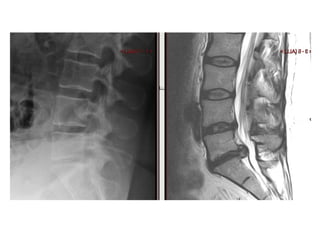

P. E.  65 years old He presented with a long history of immobility and progressive deterioration in his level of function.  Unable to feed himself, turn in bed or do any activities of daily living.  He had been bed bound for about a month. He had clear signs of cervical myelopathy